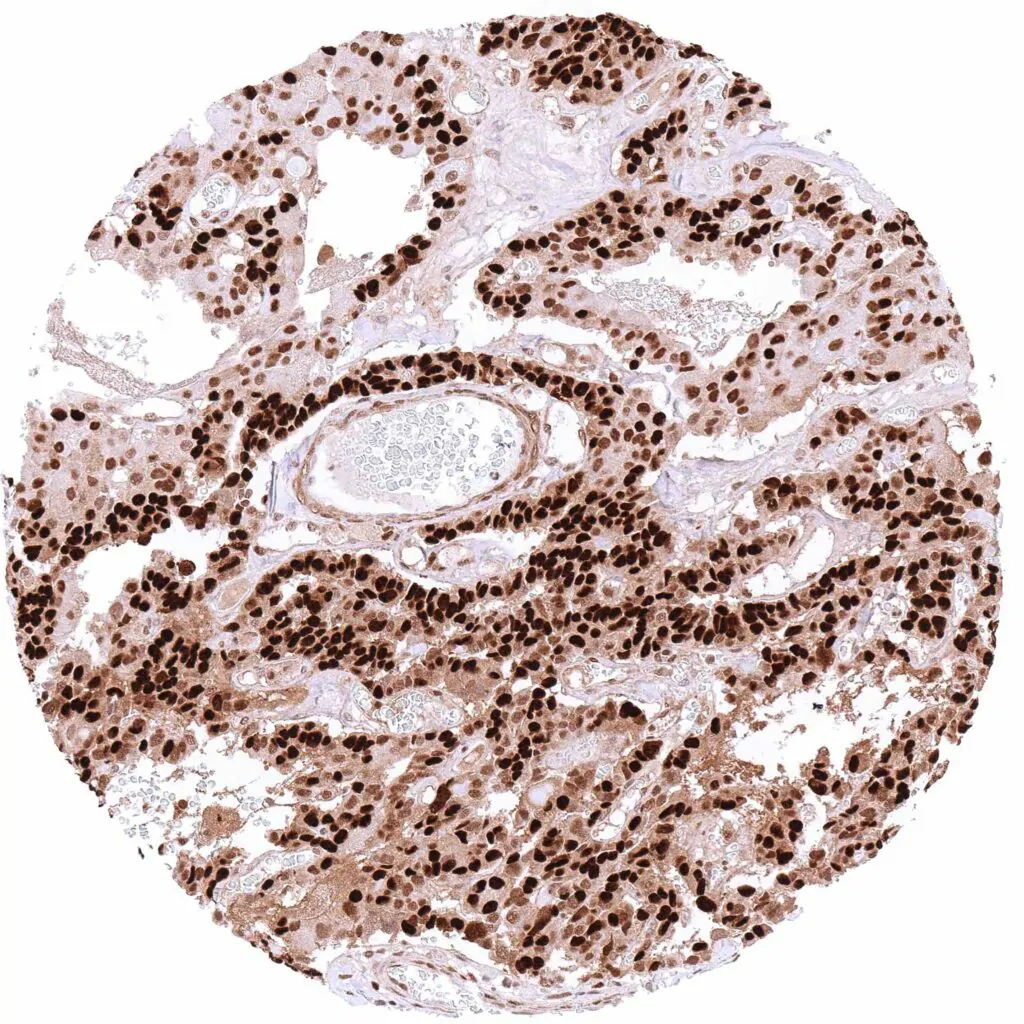

Lymph node – B-CLL with intense nuclear and cytoplasmic p27 positivity of all tumor cells.

Lymph node – Diffuse large B-cell lymphoma with strong, predominantly nuclear p27 staining of tumor cells.